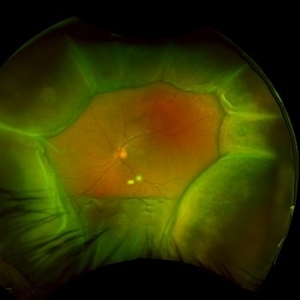

Idiopathic Uveal Effusion Syndrome

Idiopathic Uveal Effusion Syndrome

Aug 22 2024 by Jordyn Beckman

61 year old male with Idiopathic Uveal Effusion Syndrome with starry night appearance on fluorescein. 3 weeks s/p single external drainage retinotomy and 9 weeks of oral pred with recurrent choroidal effusions. Has since returned to surgery for secondary drainage retinotomy; subretinal fluid remain persistent.

Photographer: Jordyn Beckman

Imaging device: Optos California

Condition/keywords: chorioretinitis, Choroidal, exudative detachment, window defect